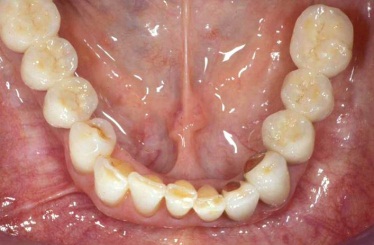

Klasickým příkladem a indikací pro použití implantátu je ztráta jednoho zubu (v tomto případě v předním – frontálním úseku) v jinak zdravém, nepoškozeném chrupu.

Nejčastější příčinou takové ztráty je sportovní nebo dopravní úraz.

Náhrada jednoho zubu pomocí implantátu je možná také v postranním úseku chrupu. Při ztrátě většího počtu zubů ve frontálním nebo postranním úseku může být mezer uzavřena větším počtem jednotlivých implantátů.

Při ošetření pomocí jednotlivých implantátů zůstávají sousední zuby neporušené – intaktní. Při klasickém ošetření pomocí můstků musejí být tyto zuby obroušeny!